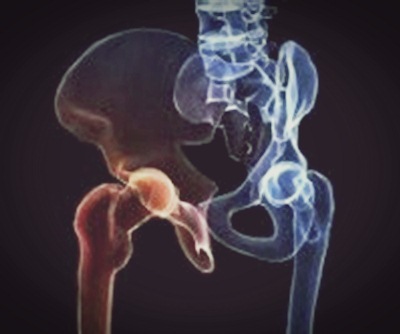

고관절 통증의 초기 증상이 뚜렷하지 않아 대수롭지 않게 넘기는 경우가 많다. 또한, 허리와 엉덩이쪽의 통증으로 허리질환으로 의심하거나 무릎 통증으로 의심하는 경우도 많다. 이렇게 오해하고 통증이 지속될 경우 더 큰 문제를 가져올 수 있다.

괴사가 심해질 경우 체중의 하중을 견디다 못해 뼈가 내려앉을 수 있으며 이때에는 엉덩이와 사타구니를 포함해 쑤시고 통증이 악화된다. 고관절을 움직이기 어렵고 걸음걸이가 뒤뚱거리거나 절뚝거리는 것처럼 보일 수 있다. 고관절을 움직이기 어렵고 걷거나 양반다리같이 다리를 벌려 앉을 때 심한 통증을 느끼게 된다.